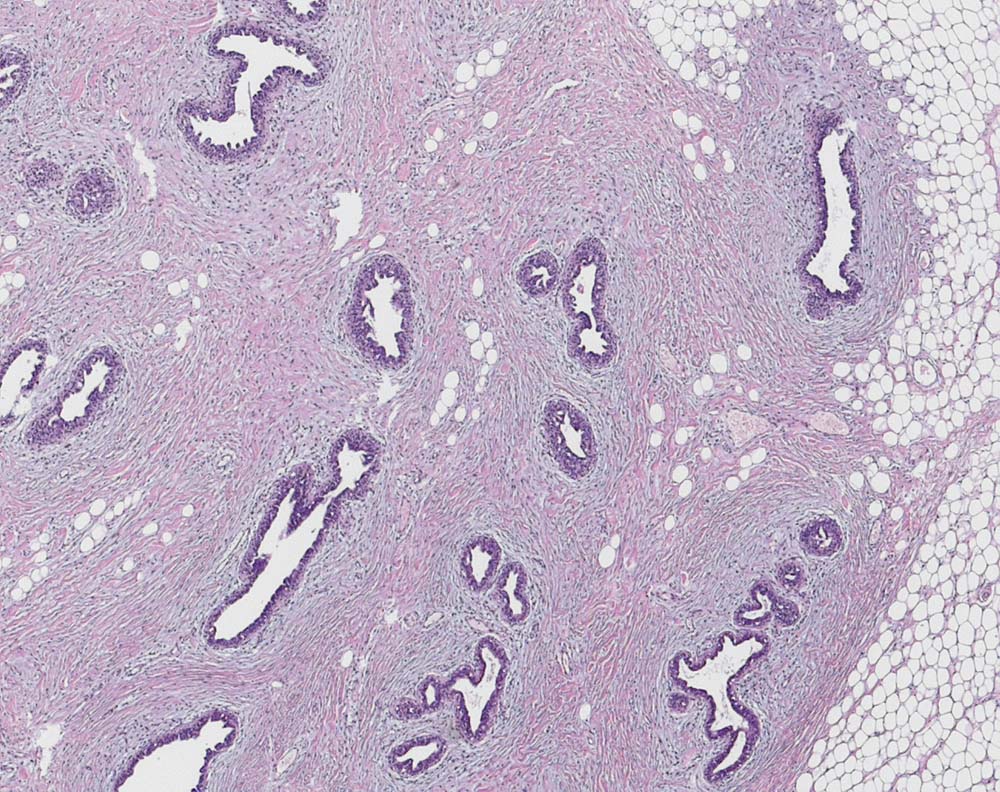

Gynäkomastoide Läsion der weiblichen Mamma

Die histologischen Veränderungen sind von einer floriden Gynäkomastie der männlichen Brust nicht unterscheidbar.

Verlust der reifen Drüsenläppchen. Ektatische Milchgänge mit mikropapillären Epithelproliferaten und einer Myoepithelschicht. Das periduktale Stroma ist myxoid aufgelockert und zellreich. Eine Kapsel ist nicht erkennbar.

Im Gegensatz zu Hamartomen und Adenolipomen weist die Läsion keine bindegewebige Kapsel auf.